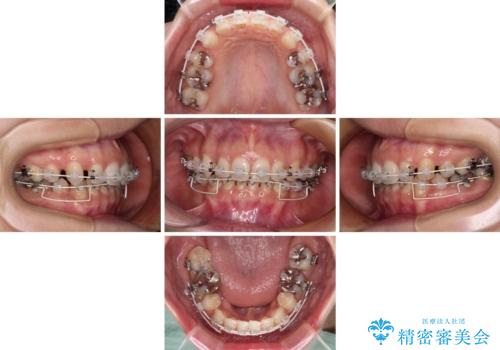

顎先に梅干し皺ができる 閉じにくい唇を抜歯矯正で閉じやすく

- 口元の突出感と口の閉じにくさを気にして来院された患者様です。

上下左右第一小臼歯4本を抜歯し、ワイヤー装置にて口元を引っ込めるよう矯正治療を行うこととしました。

奥歯が前方に傾斜していることで深く咬みこむ(ディープバイト)状態であったので、なかなか抜歯したスペースが閉じず、様々な方法でディープバイトを改善しながら治療を進めていくこととなりました。